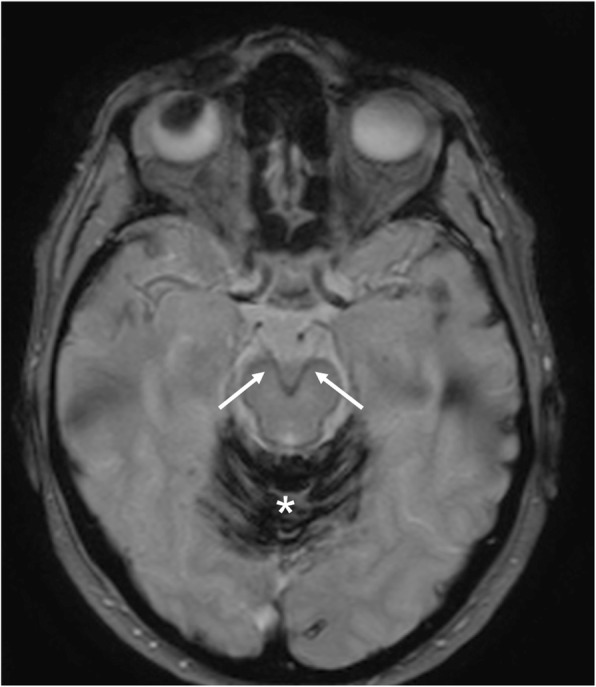

Fig. 33.

Superficial siderosis. MRI T2*-weighted axial image demonstrates hemosiderin deposition along the course of oculomotor nerves (arrows). Massive hemosiderin deposition is also visible on the cerebellar folia (asterisk)